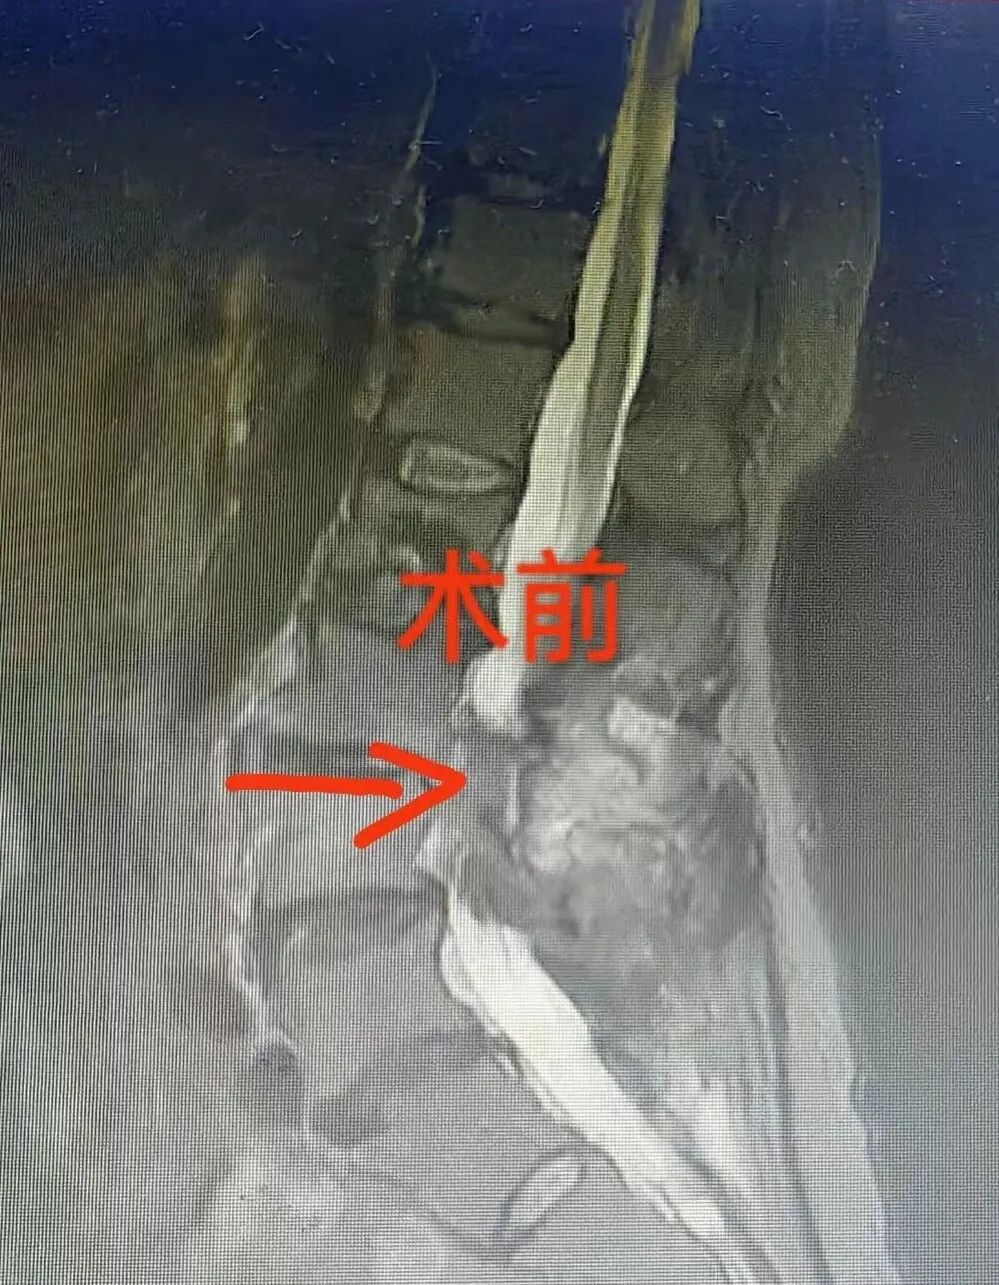

接诊后,骨科团队高度重视。经过系统的腰椎MRI检查,并结合详细的病史询问,发现杨大妈的病情较为复杂:考虑腰椎间盘术后椎间隙感染

经过周密的评估与准备,手术时机成熟。由骨科团队为杨大妈精准施行了 “L3-L4椎管减压+椎间盘植骨融合+病灶清除术” 。手术成功只是第一步,术后的康复管理与专业护理同样至关重要。在骨科医护团队的精心照护与科学指导下,杨大妈的康复进程令人欣慰: